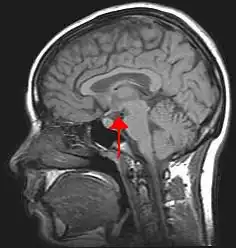

The central nervous system includes the brain and spinal cord. The brain and spinal cord are protected by bony structures, membranes, and fluid. The brain is held in the cranial cavity of the skull and it consists of the cerebrum, cerebellum, and the brain stem. The nerves involved are cranial nerves and spinal nerves.

The "Central Nervous System", comprised of the brain, brain stem, and spinal cord.

The central nervous system (CNS) represents the largest part of the nervous system, including the brain and the spinal cord. Together with the peripheral nervous system (PNS), it has a fundamental role in the control of behavior.